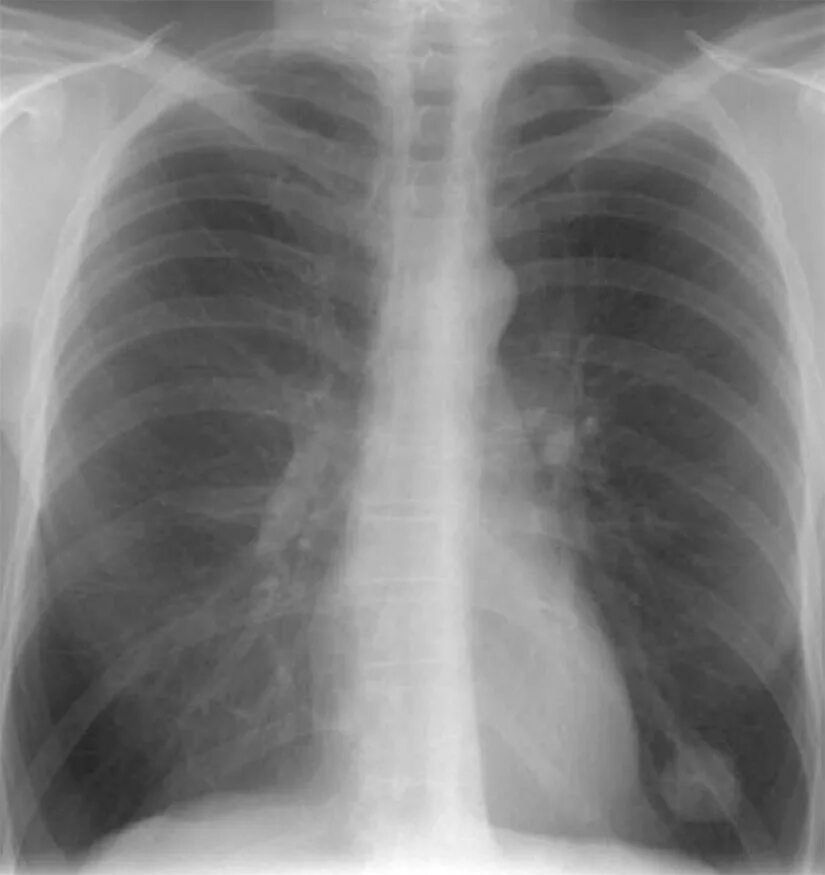

Метастазы в легких прогноз 4 стадия